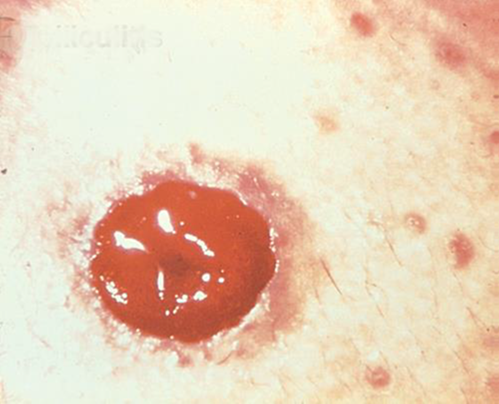

Pyoderma Gangrenosum3

Description/causes : Une maladie inflammatoire de la peau souvent observée chez les patients atteints d’une maladie inflammatoire de l’intestin (MII) telle que la maladie de Crohn ou la colite ulcéreuse.

Symptômes : Ulcères irréguliers, rouges, douloureux, infectés, avec des marges roulées rouges à violettes ; apparaissent sur les jambes, les fesses, le visage et la région péristomiale.